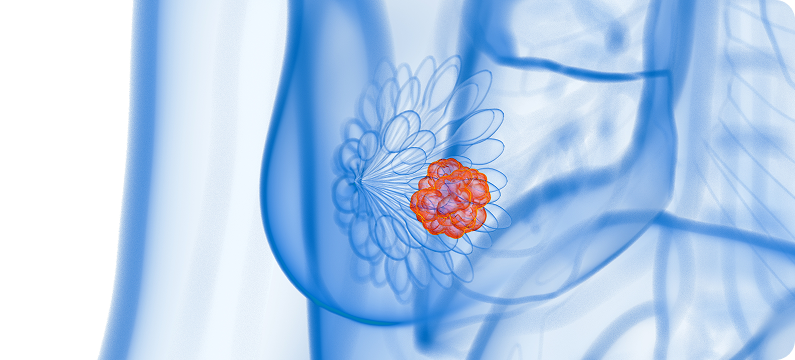

유방 · 전립선초음파는 여성의 유방 질환과 남성의 전립선 질환을 초음파로 정밀하게 확인하여,

방사선 노출 없이 안전하게 시행할 수 있어 조기 진단과 추적 관찰에 매우 중요한 검사입니다.

유방과 전립선은 다양한 질환이 발생하기 쉬운 부위로, 조기 발견 여부에 따라 치료 경과가 크게 달라집니다.

정기적인 유방 · 전립선초음파 검사는 이상을 조기에 확인하고 적절한 치료로 이어지는 가장 효과적인 방법입니다.

유방에 멍울이 만져지거나 통증이 있는 경우

건강검진 또는 영상검사에서 유방 이상 소견이 나온 경우

치밀 유방으로 추가 검사가 필요한 경우

유방암 가족력이 있는 경우

유방 결절 · 낭종의 경과 관찰이 필요한 경우

30, 40대 유방질환 고위험군 여성